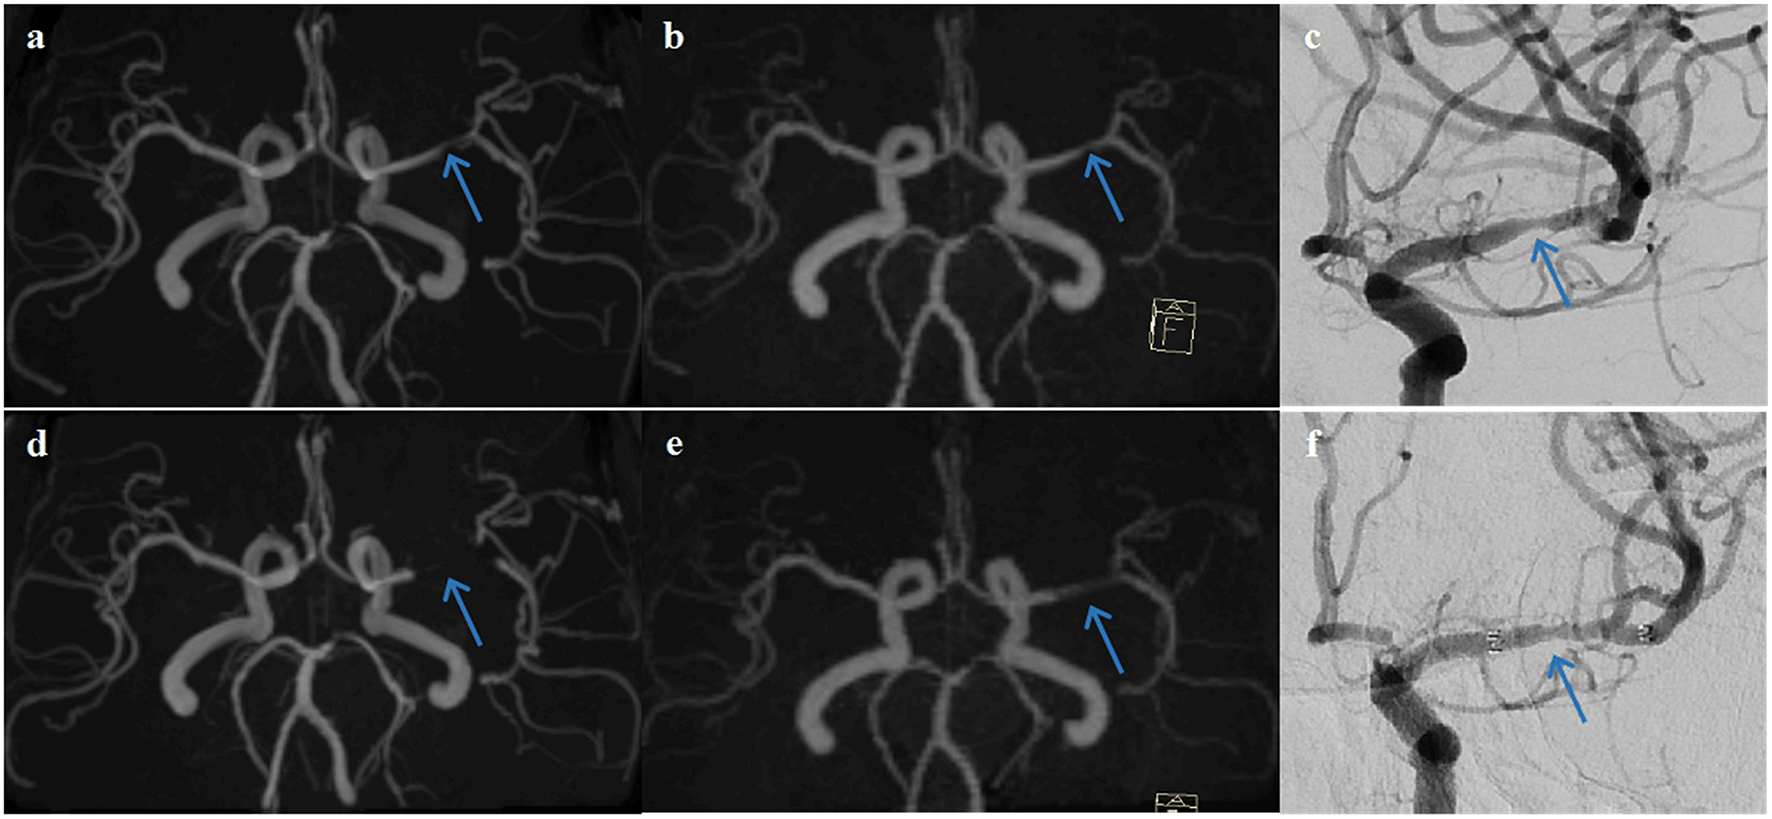

The examples from two patients having pre- and post-interventional imaging are shown in Figures 4, 5.

Figure 4

A representative case of a 63-year-old female patient who underwent stent angioplasty due to atherosclerotic stenosis of the left middle cerebral artery (MCA) at the M1 segment (blue arrows). Pre-intervention images are shown on the top row (a) TOF-MRA, (b) PETRA-MRA, and (c) DSA. The degree of stenosis was 79.8% on TOF, 65.3% on PETRA-MRA, and 68.6% on DSA. Image quality scores of the PETRA-MRA and 3D-TOF were both 4. Post-intervention images are shown on the bottom row (d) 3D-TOF, (e) PETRA-MRA, and (f) DSA. Post-intervention TOF-MRA had strong signal loss near the stent, and post-intervention PETRA-MRA had mild signal loss near the stent comparing with reference DSA. PETRA-MRA had significantly higher image quality scores than those of TOF-MRA considering flow visualization within the stents (PETRA-MRA, 4; 3D-TOF, 1) and susceptibility artifact (PETRA-MRA, 3; 3D-TOF, 1).